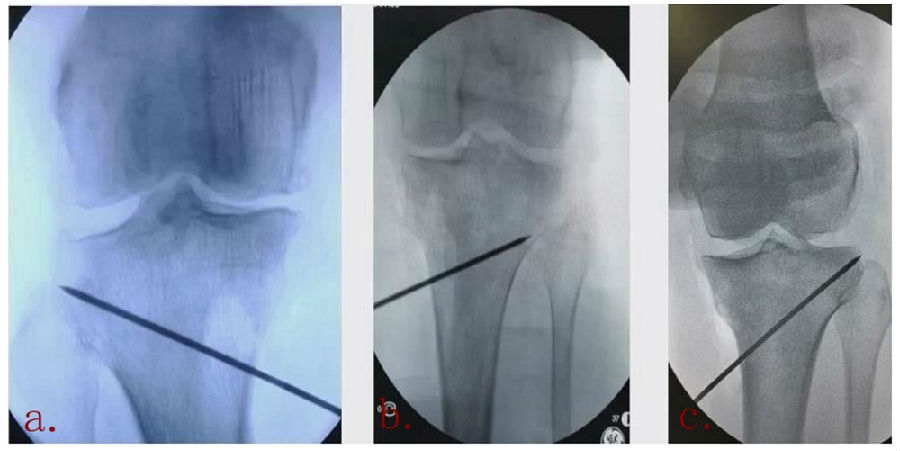

(2)Ⅱ型骨折

当出现Ⅱ型骨折时要特别注意,因为此时截骨的远端就是骨折的远端,近端只有上胫腓周围骨筋膜存在,所以相对来说Ⅱ型骨折并不稳定。

首先用拉力螺钉复位,调整好力线。然后做结构性植骨,延迟负重,所谓延迟负重就是延迟到外侧合页和上行截骨线处达到初始愈合,然后再让患者进行负重。如果不做结构植骨加延迟负重,就会出现一些非常严重的现象,如不愈合。

拉力钉复位,结构性植骨

左侧患者未植骨正常负重,术后4个月不愈合;右侧患者非结构性植骨过早负重,术后1年未愈合